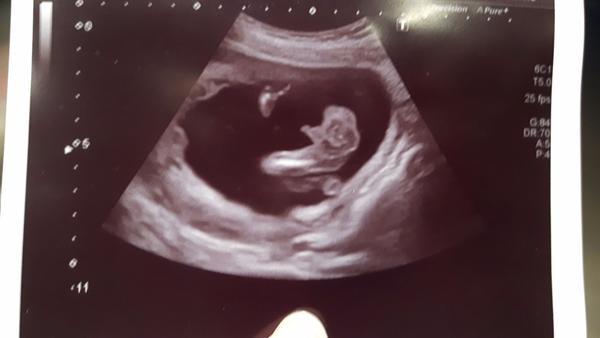

Dekuju. Ja ho tam videla jeste nez mi to rekla. Ale kdyz ted vsude ctu jak se to da zamenit s pup.snurou tak jsem znejistela 🙂

@jendurka ja tam hrbolek nevidim ☹

je to je skoda.Dr mi ukazovala tu carecku tak sem si myslela ze je to ono.Ze to tam oznacila.Jinak dekuji👍